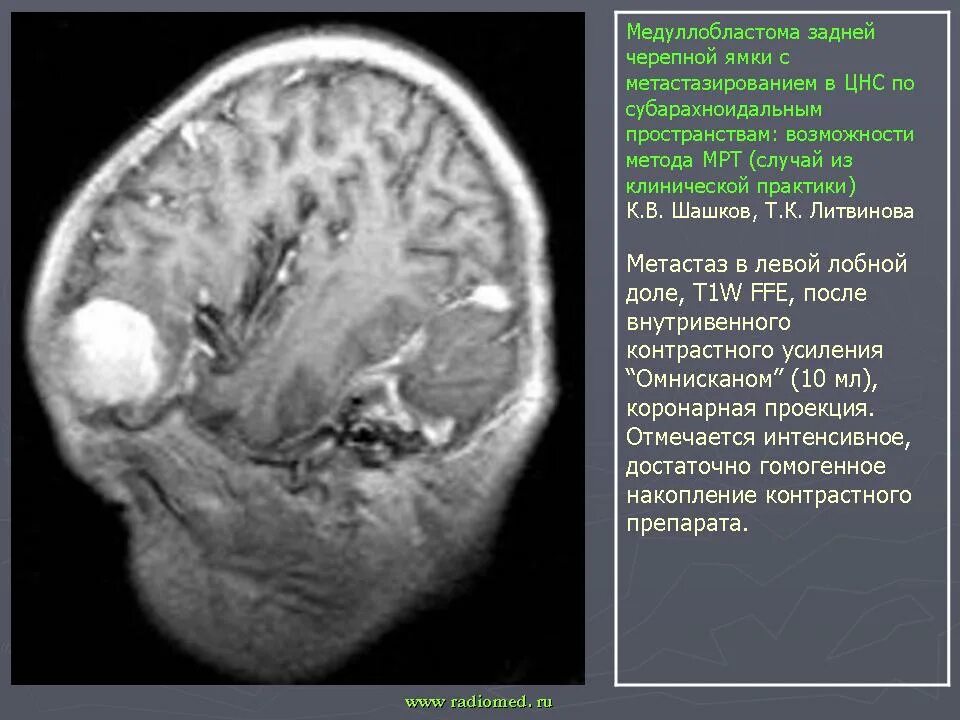

Медуллобластома это